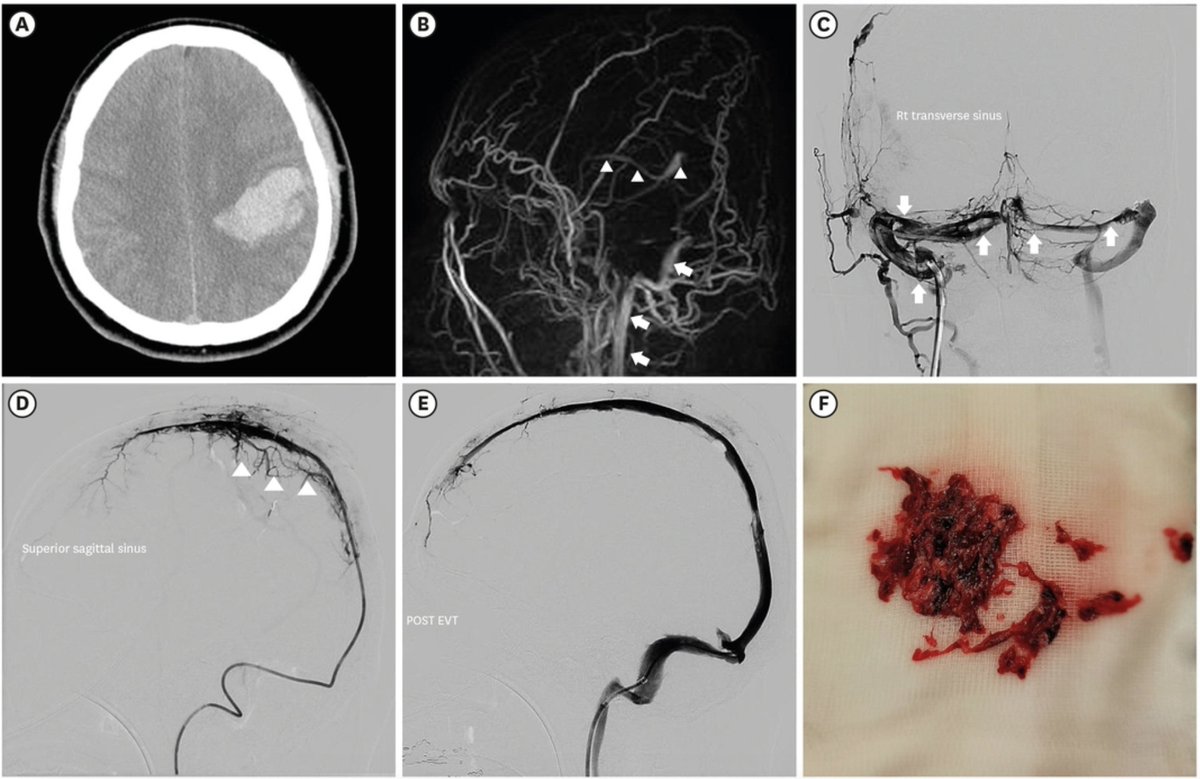

F ) Un gran numero di coaguli che sono stati rimossi mediante trombectomia meccanica endovascolare.

"Un gran numero di coaguli che sono stati rimossi mediante trombectomia meccanica endovascolare"